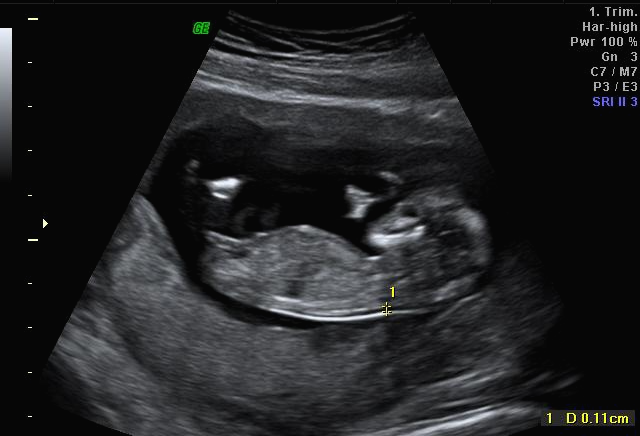

그리고 초음파 봐주시는 분께서 13주차가 되면 정확히 알 수 있으니 다음 주에 오라고 하셔서 일주일 뒤 다시 방문을 했습니다. (위에 사진은 12주 차 때 아들이라고 보여주신 초음파 사진이에요~ 화살표 보면 툭 튀어나와있는 부분을 보여주면서 아들이라고 하셨어요~)